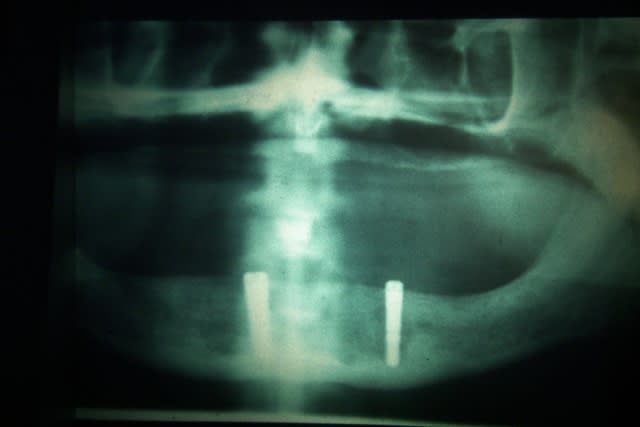

étant debutant je vous demande de me conseiller pour ce cas:femme 48 ans en bonne santé,désire implants mandibulaire pour stabiliser sa pothèse,mais j'hésite car crête fine ,

qu'en pensez-vous.

sinon je pencherais pour 4 implants voir 6 pour prévoir l’avenir (à 48 ans elle à déjà bien avancé pour la perte osseuse) , avec une barre et cavalier plutôt que boutons

Si la crete est vraiment fine : expansion, condensation (pas simple de 33 à 43)

on ne voit pas très bien sur ton cliché, mais il y a souvent moyen de ratiboiser la partie trop fine de la crête pour retrouver une largeur acceptable tout en conservant assez de hauteur (les extrémités des implants peuvent, si besoin, s'insérer jusque dans la corticale inférieure de la symphyse)

c'est quoi cette téléradiographie de profil bizarroïde? j'ai jamais vu ça, c'est ininterprétable, c'est à refaire.

ton bilan radio est faussé dès le départ, sinon fait un scanner de la mandibule.

pourrais tu nous en dire en peu plus sur l'anamnèse de cette patiente. A la vue de la téléradio de profil la crête est sacrément résorbée pour une femme de 48 ans!

Ton cas est loin très simple pour commencer en implanto :

- résorption importante de la crête ce qui induit plusieurs difficultés : d'une part la proximité du plancher avec toutes les complications que cela peut engendrer, d'autre part un placement implantaire délicat si tu ne tiens pas compte de la résorption centrifuge de la mandibule par rapport au maxillaire.

- tes traits d'incision distaux devront être également réfléchis compte tenu de la proximité crestale du foramen mentale.

- penses à l'environnement gingival periimplantaire et évites de placer tes implants dans la muqueuse du plancher buccal. Il est pas impossible que de la muco préimplantaire soit indiquée dans ton cas (difficile à apprécier avec la photo clinique fournie ;-D )

La hauteur de crête est très rarement un probléme au niveau de la symphyse mandibulaire. Je ne vois donc pas trop l'intérêt de s'embêter avec une expansion crestale horisontelle (surtout si tu veux faire un overdenture comme tu sembles l'avoir dit dans ta présentaion initiale du cas). Compte tenu du terrain très certainement parodontopathique de ta patiente je te conseille fortement d'aplatir ta crête de facon à obtenir un volume osseux vestibulo-lingual suffisant et une crête plate (te permettant ainsi de positionner tes implants sur un même plan horisontal)

Je ne vois pas trop l'intérêt d'aller chercher un ancrage bi-cortical dans ce cas là. Surtout quand on débute en implanto.